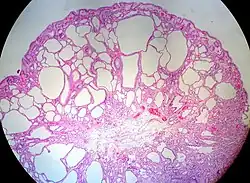

Juvenile Polyp Upper GI tract and colon Cystically dilated glands with expanded lamina propria Not inherently, may develop dysplasia

Juvenile polyposis syndrome, identical polyps in Cronkhite–Canada syndrome